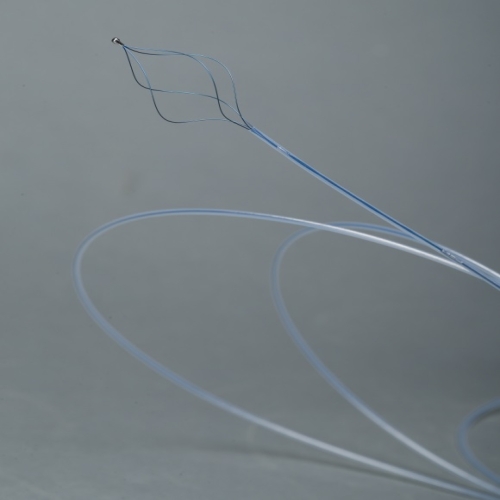

取石网篮 SF-15/30-7-P-A